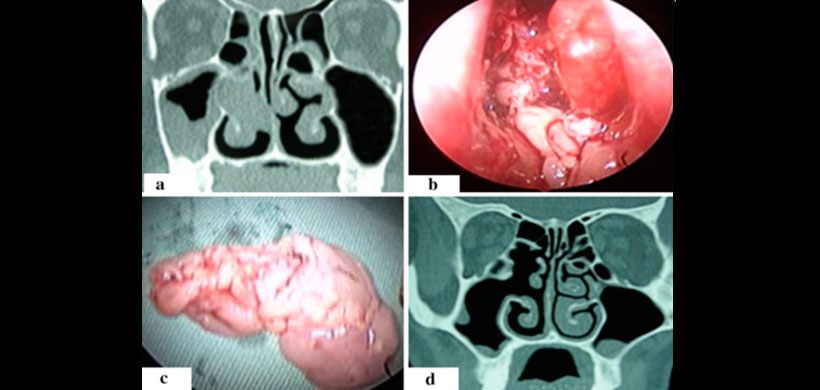

En la presente investigación se menciona dos casos en los cuales existe un tumor que involucra cavidad nasal, complejo osteomeatal, pared medial y posterior del seno maxilar, senos etmoidales y extensión mínima en el seno frontal. Los senos esfenoidales fueron manejados exclusivamente por endoscópico transnasal. (Figura 1)